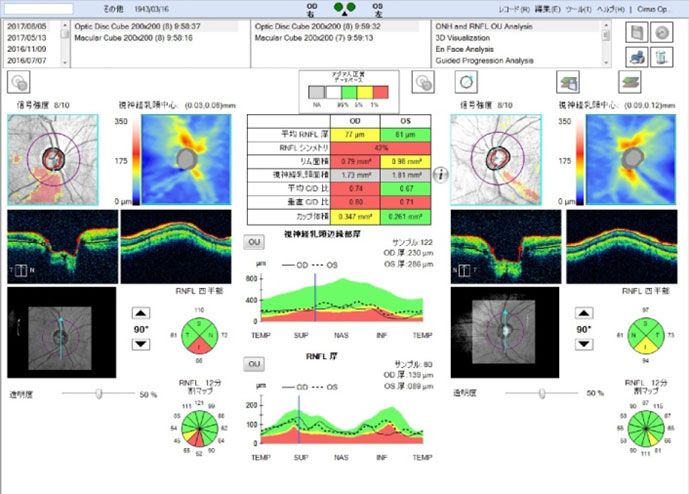

最近この判断を助ける上での画期的な検査機器が登場しました。眼底三次元画像解析装置(OCT)とよばれるもので、近赤外線レーザーを用いて眼底の視神経乳頭の変化や網膜視神経線維層の厚みの変化を正確に判定出来るようになったのです。当院はOCTをいち早く導入し、緑内障を示唆する異常がありながらも、通常の視野検査でまだ視野欠損を認めない状態である前視野緑内障(preperimetric glaucoma:PPG)を検出することができます。緑内障は早期発見早期治療が基本ですので、超早期緑内障の治療を早期に発見をして経過観察を行っていくことは、緑内障の患者様にとって大切であると思っております。

視神経乳頭解析

視神経乳頭解析

緑内障の早期発見の為に、特に前視野緑内障の検出に非常に有用なOCT検査を精密視野検査やその他の検査と併せて行っております。ドックや健診で乳頭陥凹と指摘された方は勿論、近視の強い方や、家族に緑内障患者さんがおられる方は特に早めの検査を受けるようにお勧めしております。病状によりハンフリー視野検査 ゴールドマン視野検査 視神経乳頭解析 GCAを3〜6ヶ月に行い、進行をグラフ化して経過観察を行います。